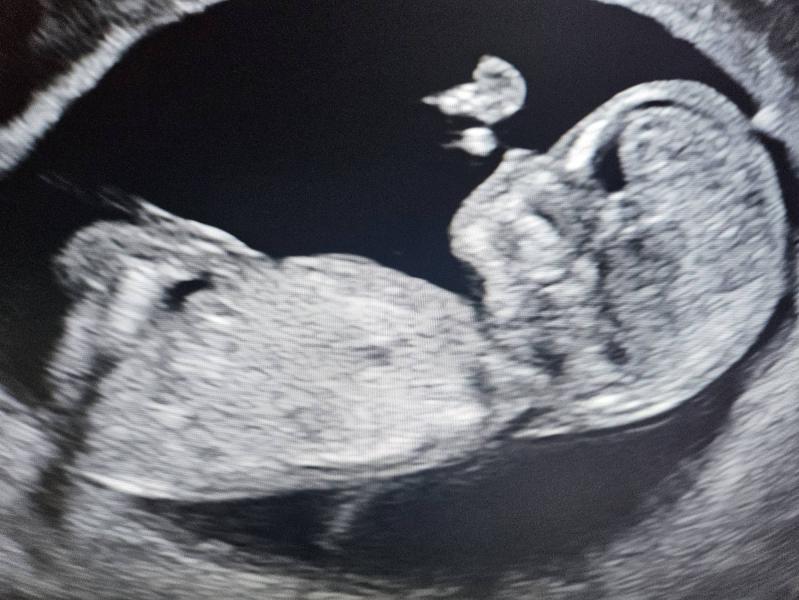

Все что осталось у меня от моего малыша, это только фото узи. Помню как плакала когда мне показали экран где малыш шевелится... Тогда я даже представить не могла, что впереди меня ждет, и что мой Лев родится на 18 неделе, потому что у него будет куча потологий....Иногда думаю, почему это со мной произошло, почему мне судьба дала это испытание, почему я должна была выбрать, когда мой сын умрет, в 18 недель или сразу после родов. Почему со мной случились две неудачных беременности, сначала беременность рубцовая которая закончилась в феврале, потом беременность с синдромом эдварса, которая прервалась в ноябре. На еще одну беременность я пока не готова решится, не хочу больше испытывать боль...